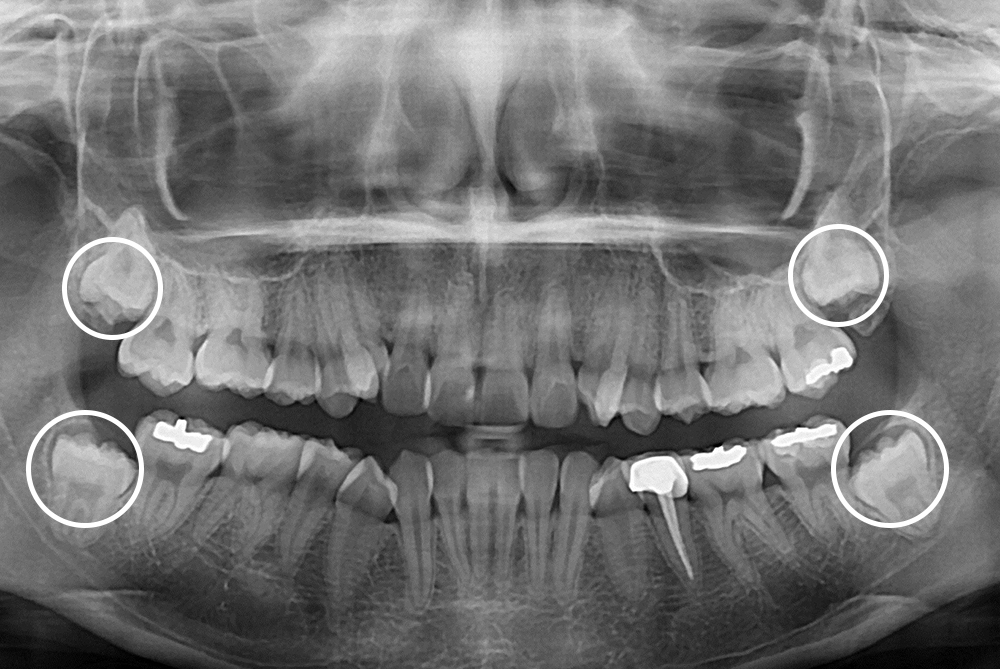

[사랑니] 매복 사랑니 발치

치료전 : 2017-02-02